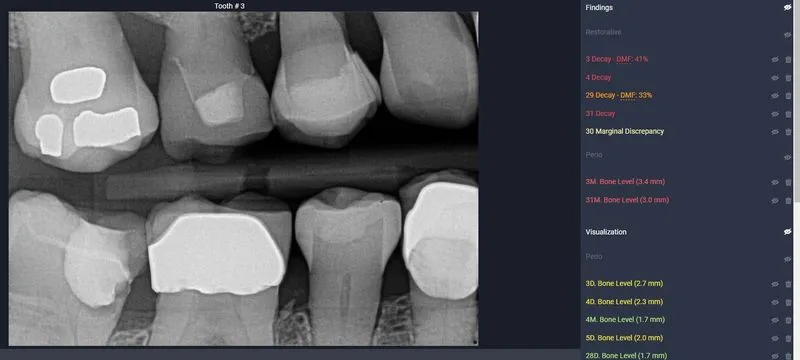

AI activated, showing Decay in red, and Yellow lines indicate bone loss

Not only does our AI serve as your trusted dental confidant, offering a secondary assessment that's as reliable as your favorite dental hygienist, but it's also the go-to tool for insurance companies to verify the quality of your X-rays. But wait, there's more! Our AI isn't just a one-trick pony. It possesses the prowess to spot decay, detect infections, measure bone density for signs of bone loss, identify tartar buildup, and flag any abnormalities that warrant further inspection.